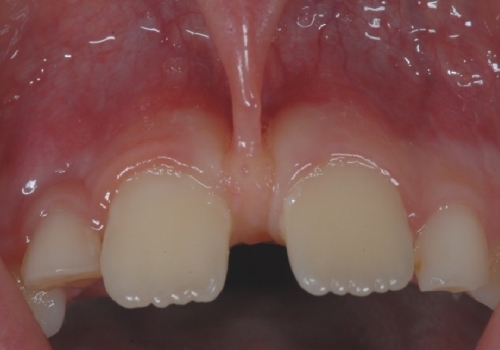

Frenulum (yüyən), diş əti toxuması (gingiva) ilə dil, dodaq və yanaq arasında yerləşən, toxumaları bir-birnə bağlayaraq hərəkətlərini sərhədləndirən yumuşaq selikli qişa toxumasıdır. Frenulum normal ölçülərdən böyük və qalın olduqda və ya diş əti kənarına yaxın yerləşdikdə bəzi narahatlıqlara və məhdudiyyətlətə səbəb ola bilir. Diş əti çəkilməsi, estetik məhdudiyyət, diastema, çıxan protez istifadə edən şəxslərdə protez fiksasiyasının məhdudlaşması və s. durumlar bununla bağlı ola bilir.